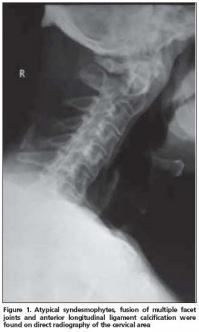

Anterior longitudinal ligament calcification, fusion of multiple facet joints and atypical syndesmophytes were found on cervical spine X-rays (Figure 1) and coarse, asymmetrical syndesmophytes were seen on thoracic (Figure 2) and lumbar spine (Figure 3) X-rays. No abnormalities suggesting PsA or gout were seen on hand and foot radiographs. The magnetic resonance imaging (MRI) of the sacroiliac joint and computerized tomography (CT) of atlanto-axial joint were normal.